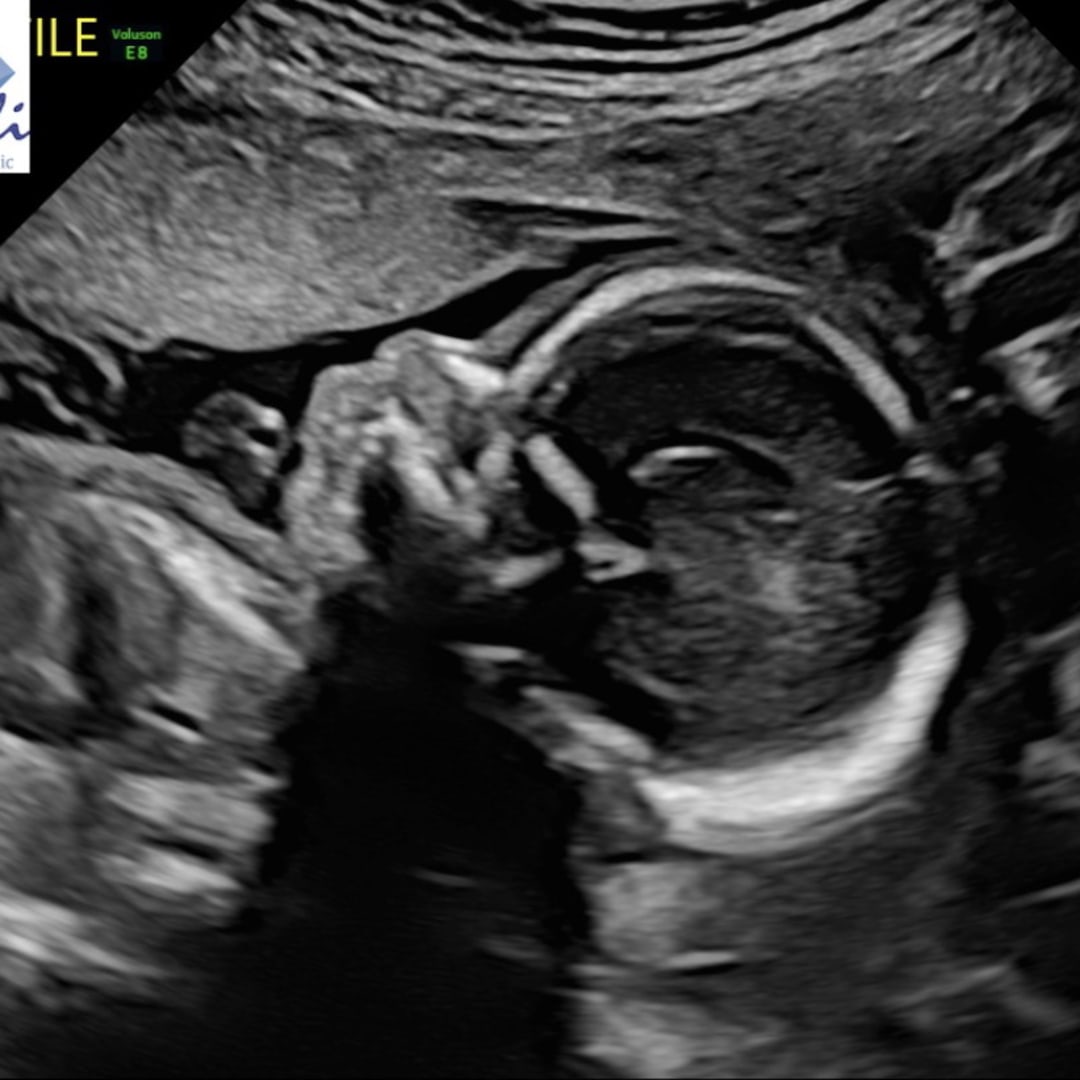

Baby Washburne

Alissa & Adam Washburne

Canton, OH

May 7, 2026

We are so excited to welcome Baby W in early May! Our hearts are so full knowing how loved this baby already is. Thank you for your love, support, and generosity - it means the absolute world to us! With love, Adam & Alissa 🫶🏼